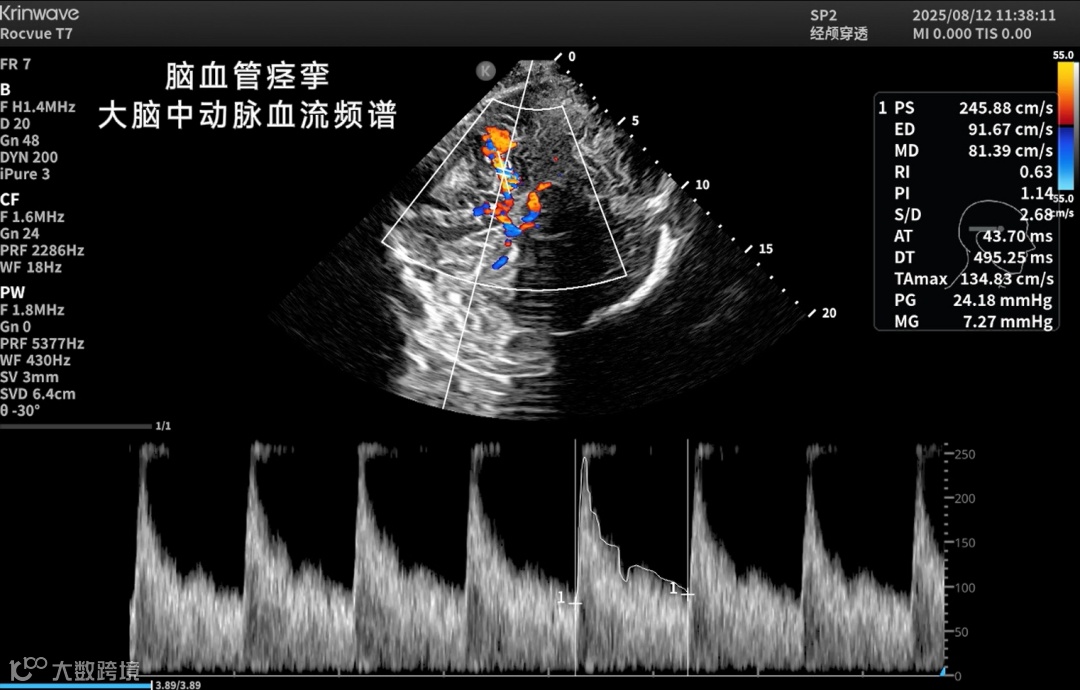

凭借更强的穿透力、更高的帧率和更清晰的组织呈现,鲲为颅脑超声能提供优质的颅内二维影像和血流影像,在更多临床与科研场景中具备可被依赖的影像表现:

也正因为这份突破,Rocvue H系列超高端科研超声在神经重症、脑出血监测、帕金森诊断、儿科管理、神外术中评估、颈脑一体化观察,以及神经系统疾病科研等场景中,都展示出颅脑超声更多可被依赖的未来图景。